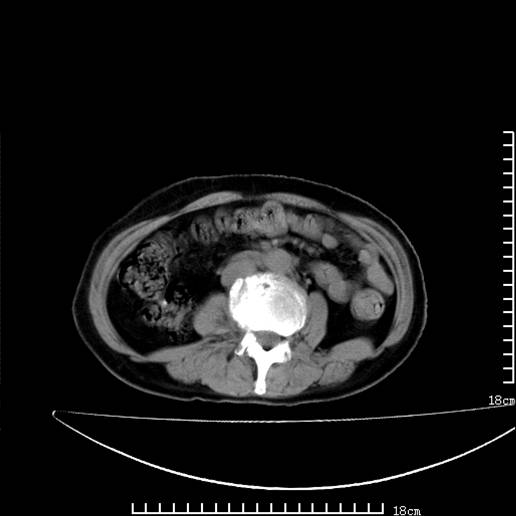

以下是引用pujunzhi在2008-5-30 15:31:00的发言:[br]异位肾—盆腔肾。当看到肾窝无肾脏时,要想到孤立肾和异位肾,异位肾最常见是盆腔肾,偶见胸腔,易误认为肺占位,只要想到就不会漏诊。建议增强扫描。